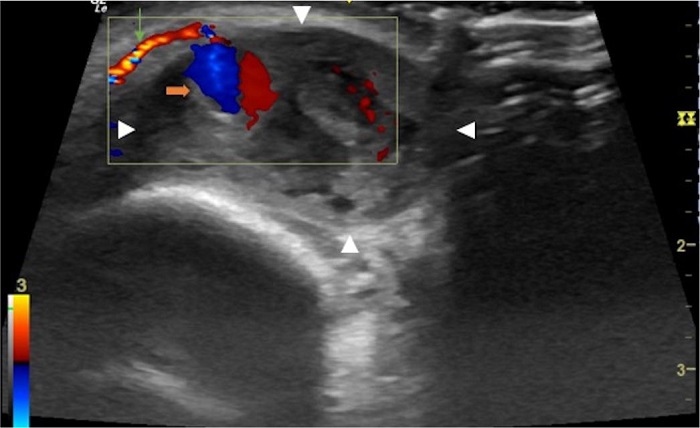

O hematoma à direita apresentava ecotextura heterogênea e media 2,9 x 1,4 x 2,2cm. No interior deste nódulo, destacava-se outro nódulo anecoico, de limites bem definidos, medindo 0,7 x 0,7cm, que apresentava fluxo bidirecional ao exame com Doppler colorido, fluxo alimentado pela artéria supratroclear direita que, por sua vez, localizava-se superficialmente na periferia do hematoma (distando 0,3cm da epiderme) (Figura 5). À esquerda, o hematoma apresentava ecotextura mais homogênea em relação ao lado contralateral, media 2,2 x 1,3 x 1,8cm, e a artéria supratroclear esquerda localizava-se profundamente (distando cerca de 1,0cm da epiderme) na periferia do hematoma.

Junto à artéria supratroclear esquerda, observou-se pequeno nódulo, medindo 0,2 x 0,2cm, com fluxo bidirecional ao exame com Doppler colorido (Figura 6). A visualização das imagens nodulares junto às artérias, associada à presença de fluxo colorido bidirecional ao Doppler (sinal do yin-yang), levou ao diagnóstico de pseudoaneurisma de artérias supratrocleares.